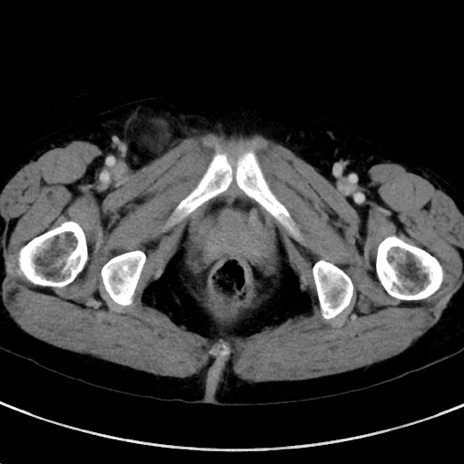

症例23(横断像)

症例

【症例】70歳代女性

【主訴】下腹部痛・嘔吐

【現病歴】2日前より腹痛あり。昨日嘔吐あり。症状改善しないため来院。

【既往歴】胃GISTに対して胃部分切除後。

【身体所見】BT 37.1℃、BP 128/77mmHg、腹部:平坦・軟、下腹部に圧痛あり。

【データ】WBC 10200、CRP 0.31